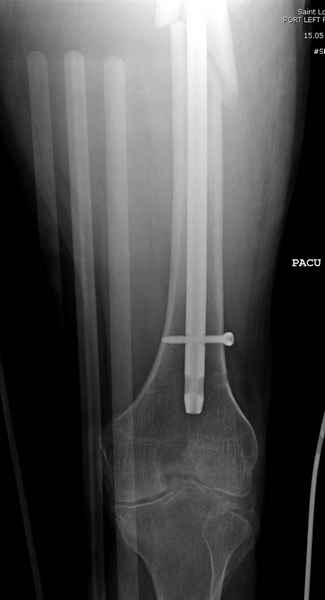

Среди русскоговорящих коллег Ортофорум стал одним из мест, где многие из нас черпают знания для решения своих ежедневных проблем в виде практических советов и обмена опытом. Кроме таких советов, Ортофорум стал источником новых познаний среди ортопедов, особенно по редко встречающимся состояниям в ортопедии. Продолжая традицию, я хотел бы представить редко встречающий случай перелома бедра у больного с гемофилией. Больному 42, гемофилия типа А, из истории упал с высоты около 1,5 метра, переправлен из другой больницы. По происхождению мексиканец, 10 лет назад по поводу артроза пр. коленного сустава в Мексике сделано протезирование, которое закончилось ампутацией выше коленного сустава. При поступлении бедро напряженное, сосудистых и неврологических расстройств нет. На рентгенограмме оскольчатый перелом бедра с вовлечением проксимальной спирали в шейку бедра. Хотели бы знать тактику ведения подобных больных и на что надо обратить внимание? Djoldas Kuldjanov, MD Department of Orthopedic Surgery St. Louis University Medical Center

Учитывая, что случай ургентный, больной поступил вечером, не стали делать вытяжение и срочно провели операцию по фиксации перелома бедра антеградным штифтом Versa Nail от DePuy.

Для профилактики дальнейшего раскола в шейке предварительно во время проксимального рассверливания спереди и сзади провели временные спицы, которые в дальнейшем были заменены на шурупы (miss nail method)